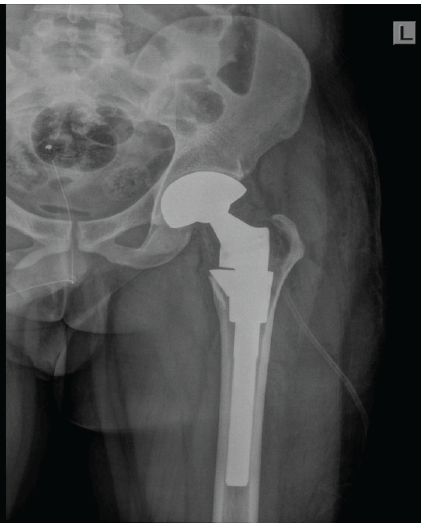

The acetabular cartilage was normal without any tumor involvement. Preparation for the acetabulum was done and dual mobility acetabular shell of size 51 was inserted. On the femoral side, after preparation of the femoral canal, a modular hip stem (SROM) size 18 × 13 calcar replacement standard stem and femoral sleeve 18F was used. Acetabular liner of corresponding size (51 × 28 mm) and femoral head 28/0 was locked using a locking mechanism, and hip joint was reduced. Hip joint was found to be stable in all directions [Fig. 5].

Figure 5: Immediate post-operative X-ray shows well positioned total hip replacement prosthesis with post curettage defect in the medial border of greater trochanter.